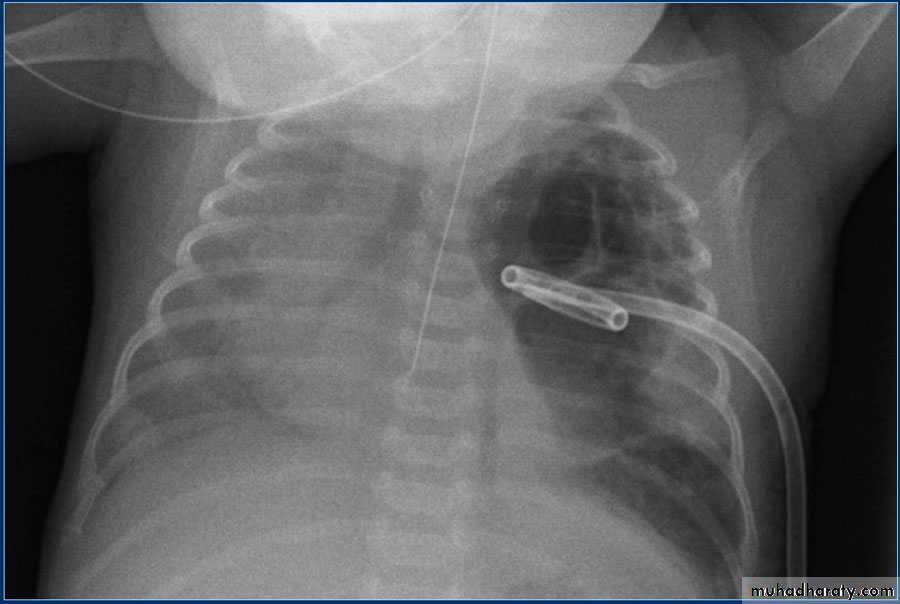

Pneumothorax

!! pneumothorax